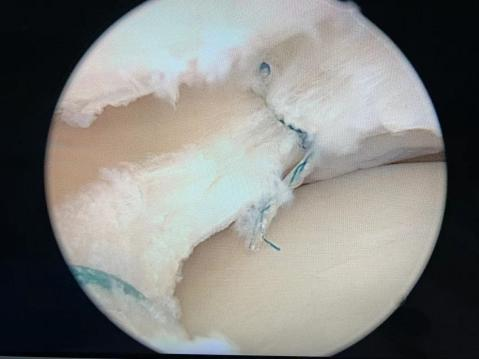

以肩袖损伤的病人为例,很多患者可以进行肩关节镜微创手术来进行治疗,效果非常好。关节镜手术是将具有照明装置的透镜金属管通过很小的切口由自然腔隙进入关节腔内,可以在高清显示器监视下非常直观的观察关节腔内的病变情况和严重程度,全面检查和清理修复病损,是一种兼具诊断和治疗两种功能的微创技术。

运动医学以微创为核心理念,关节镜为主要治疗工具,采用全关节镜下或关节镜辅助下的微创技术,治疗各种运动损伤和退变引起的关节内外相关的疾病以及后期康复。相对于传统切开手术主要有以下优势:1、损伤小,术后疼痛轻,恢复快;2、对关节内结构的观察更全面、更清晰;3、兼具诊断和治疗两种功能。